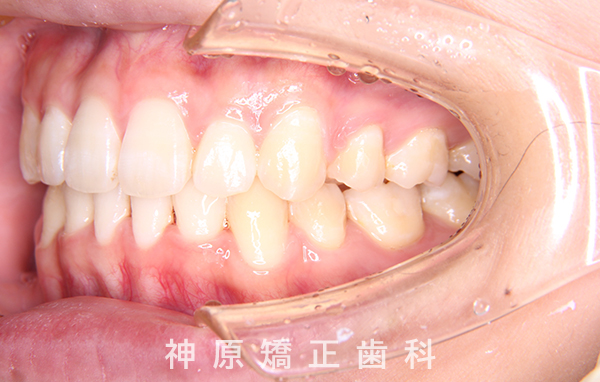

治療経過1年後

抜歯を伴う矯正治療について

今回の矯正治療を行う上で、矯正精密検査の結果口元の突出感の改善と下の歯のガタガタを改善するために小臼歯を抜歯する必要があると判断いたしました。

患者様、ご家族にも十分に説明をおこない、矯正治療のゴール設定に同意を得て矯正治療を開始いたしました。